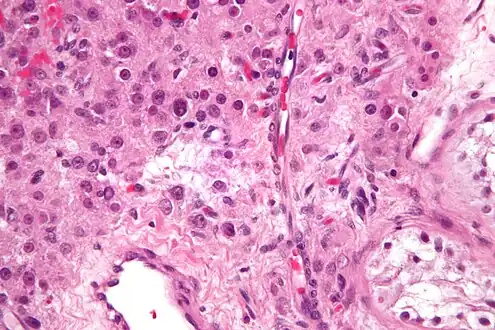

Intermediate magnification micrograph of a Leydig cell tumour, H&E stain High magnification micrograph of a Leydig cell tumour, H&E stain

Leydig cells may grow uncontrollably and form a Leydig cell tumour. These may be hormonally active, i.e. secrete testosterone. The function of Reinke crystals is unknown, but they appear in the case of Leydig cell tumours.[5] They are found in less than half of all Leydig cell tumors, but when present, they may serve to confirm the diagnosis of a Leydig cell tumor.[10][11] No other interstitial cell within the testes has a nucleus or cytoplasm with these characteristics, making identification relatively easy.

While any age is susceptible to a Leydig cell tumour, Leydig cell tumours are more common in people aged 5 to 10 and 30 to 35.[12] A Leydig cell tumour in a child usually causes precocious puberty.[12] About 10% of boys with the tumour have gynecomastia.[12] Although a Leydig cell tumour is always benign in children, it is malignant in 10% to 15% of adults.[12] It is the most common testicular cancer of non-germ cell origin.[13]